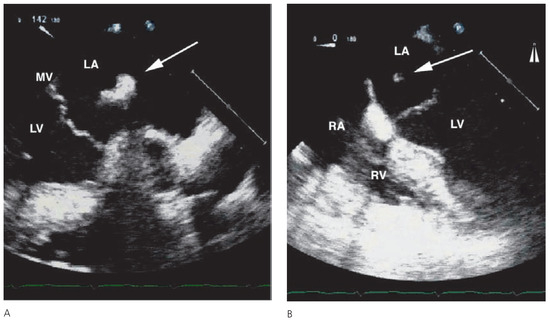

Mysterious Floating Structure in the Left Atrium After Coronary Artery Bypass Grafting

by Pascal Koepfli, Frank Enseleit and Rolf Jenni

A 60-year-old male patient was referred to our hospital for coronary artery bypass graft surgery due to prior subacute myocardial infarction and subsequently angiographically diagnosed 3-vessel coronary artery disease [...] Full article

Show Figures

Figure 1